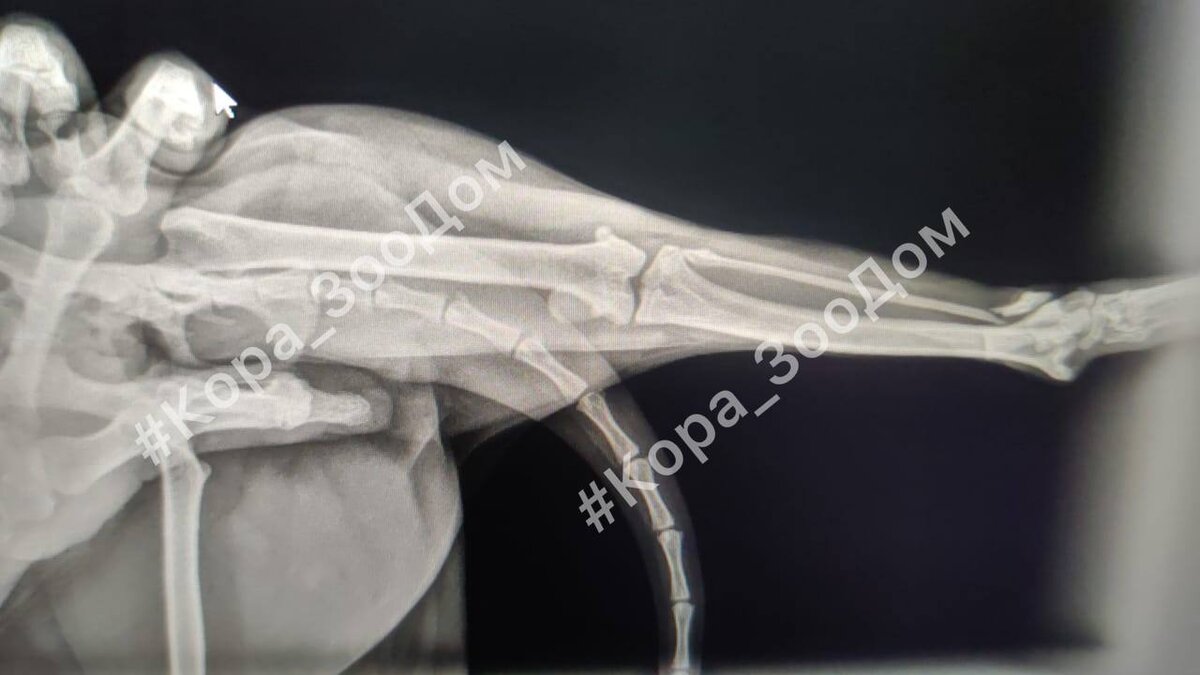

Ветклиника, рентген, консультация хирурга: перелом малоберцовой кости, большеберцовая вылетела из сустава - девочке было настолько больно, что даже снимки пришлось делать под седацией. Мы не знали, как всё произошло, но точно знали, что девочке нужна помощь. И чем скорее, тем лучше. Знали, что это будет дорого, но понимали, что это необходимо.

День операции: наркоз, надрез, оценка ситуации и понимание того, что в реальности всё намного хуже, чем на снимке - никакая металлоконструкция не удержит сустав, нужна пластина и повторная операция. Всё это время от ужасной боли малышку спасали только капельницы.